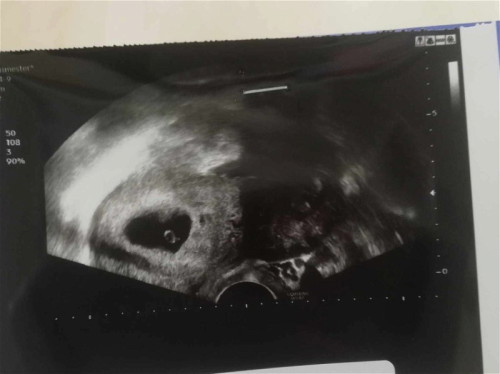

ตอนไปซาวน้อง6สัปดาห์ หมอบอกไม่เจอตัวเด็ก เเล้วในถุงตั้งครรภ์คือจุดอะไรค่ะ น้องจะมีโอกาสเป็นตัวไหมค่ะ เราเเพ้ท้องปกติค่ะเเต่รู้สึกว่าท้องไม่เปลี่ยนเลย (หรือเป็นเพราะท้อง2หนังท้องหนา) แม่ๆคนไหนมีประสบการณ์เล่าให้ฟังหน่อยค่ะ หมอนัดซาวอีกที25นี้ค่ะ เเต่เเอบกังวล